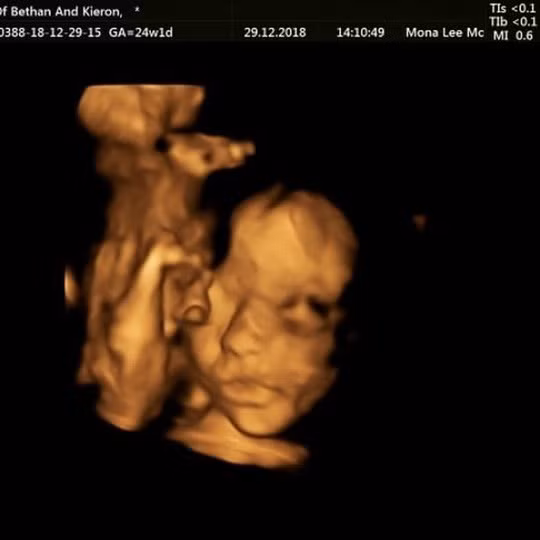

Kết quả siêu âm cho thấy thai nhi bị tật nứt đốt sống. Nếu không được chữa trị, nó có thể ảnh hưởng đến khả năng đi lại của đứa bé. Ảnh: Facebook.